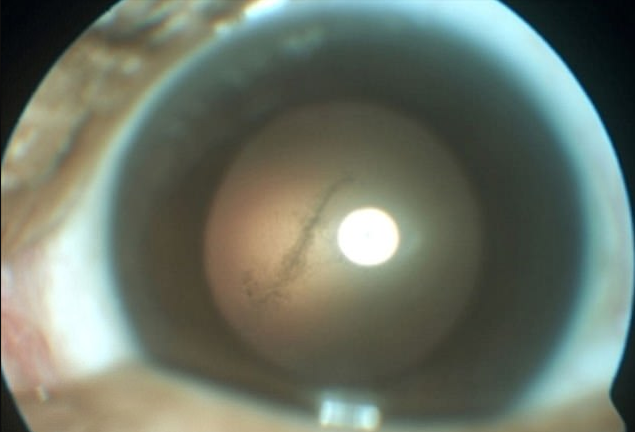

Suýt mù mắt, nhận quả đắng nhớ đời vì ăn thịt lợn chưa nấu chín

Người đàn ông này phải nhận "quả đắng" nhớ đời vì những miếng thịt lợn chưa nấu chín trong bữa tiệc cùng người thân, bạn bè.

Ông Trần Đắc Phu (Cục trưởng Cục Y tế dự phòng, Bộ Y tế) cho biết, năm 2017, cả nước ghi nhận 171 ca mắc bệnh liên cầu khuẩn lợn, trong đó có 14 ca bệnh nhân không qua khỏi.